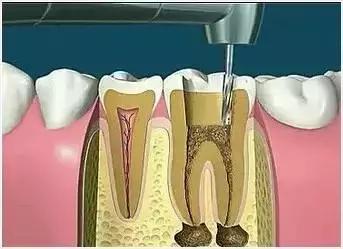

2、揭开髓腔

去净腐质和原有充填物、揭净随顶,看到整个髓底解剖结构以便后续治疗顺利进行。